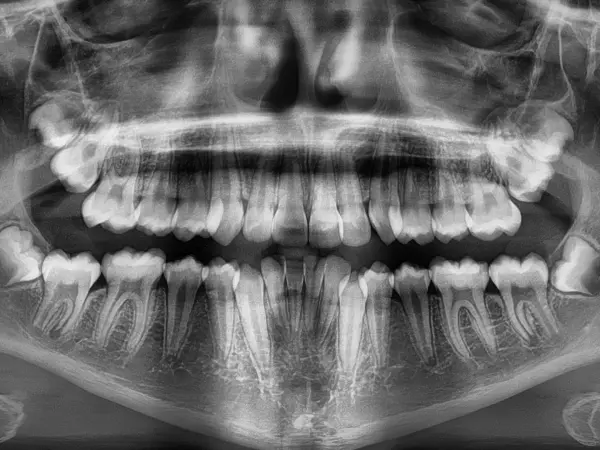

An overbite is a vertical-plane overlap between the top teeth and the bottom teeth. While a small overbite is necessary for a proper bite, it shouldn ??t overlap too far: the top teeth should close over and in front of the bottom teeth.

An overlap of more than 2-3 mm is considered an excessive overbite and should be treated by a licensed experienced orthodontist.

Orthodontists measure the severity of the overbite on a percentage scale based on the degree of overlap between top and bottom teeth: the overbite could be 30%, 50%, or 100%. The larger the percentage, the more severe the overbite, and more complex treatment is required.

An impinging overbite is considered the most severe form of overbite: this condition causes the lower teeth to touch the palate behind the upper teeth when the mouth is closed, which slowly damages the bone surrounding the upper front teeth. This can result in the loss of the upper front teeth and/or excessive trauma to the teeth.